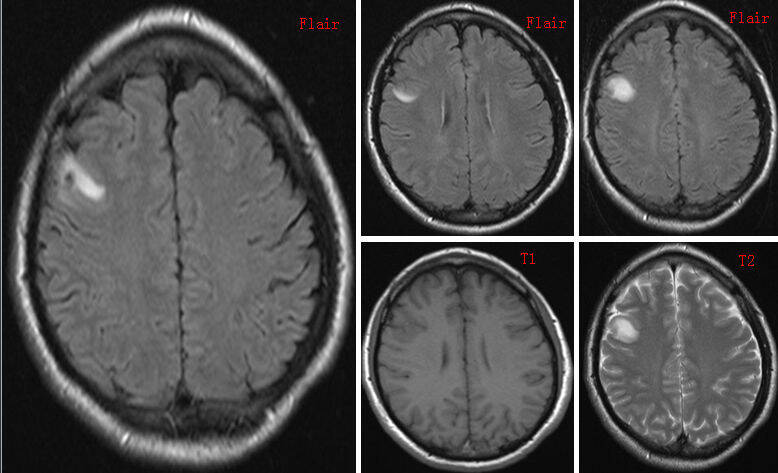

头部核磁共振显示弥漫性高强度囊性分隔脑实质、脑室内和眼后区域的病变(图A)。这些病变具有“囊肿带点征”的外观,或偏心头节是神经囊虫病的特征。大腿的冠状位MRI也显示大量高强度病变(B图)通过酶联免疫吸收剂提取血清和脑脊液化验。从腓肠肌上切除一个椭圆形半透明囊肿囊肿的组织病理学检查(C组)证实诊断为囊虫病。